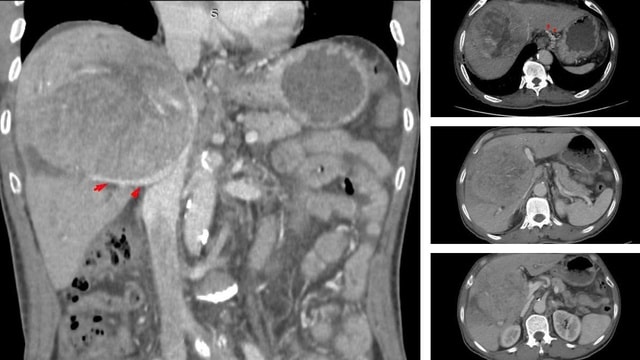

Khối u khổng lồ chiếm gần hết nhu mô gan, chèn ép rốn gan và tĩnh mạch, khiến bệnh nhân bị phù chân và cổ chướng.

BSCKII Nguyễn Trường Giang, Phó Giám đốc Trung tâm cho biết: "Khối u khổng lồ chiếm gần hết nhu mô gan, chèn ép rốn gan và tĩnh mạch, khiến bệnh nhân bị phù chân và cổ chướng".